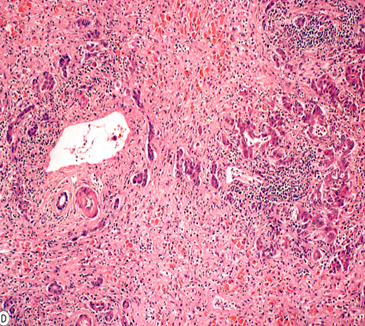

(1)光镜:①肝细胞大片(坏死面积≥2/3)或亚大片(≤1/2)坏死。坏死多由小叶中央开始,周边有少量残留的变性肝细胞。

②慢性炎细胞浸润伴肝窦扩张、充血及出血。

③枯否细胞增生肥大,小胆管增生伴淤胆。

④肝细胞再生不明显

(1)光镜:①肝细胞大片坏死伴结节状再生为特征。

②慢性炎细胞浸润及间质纤维、胆管增生明显,有淤胆现象。